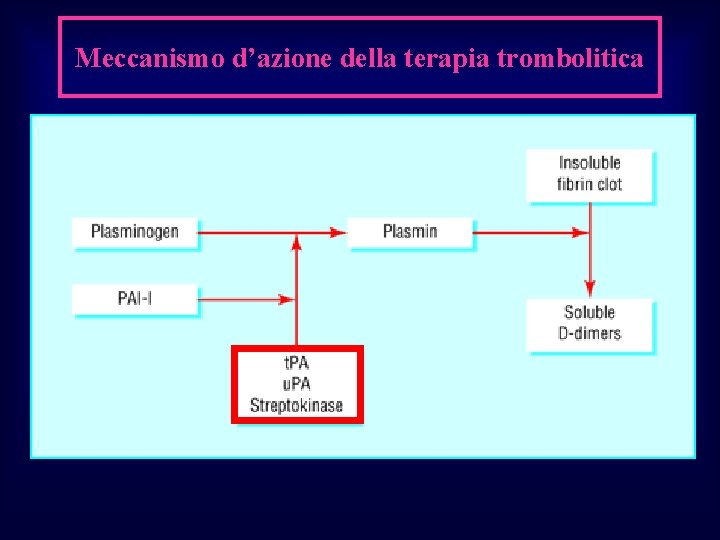

Meccanismo d’azione della terapia trombolitica